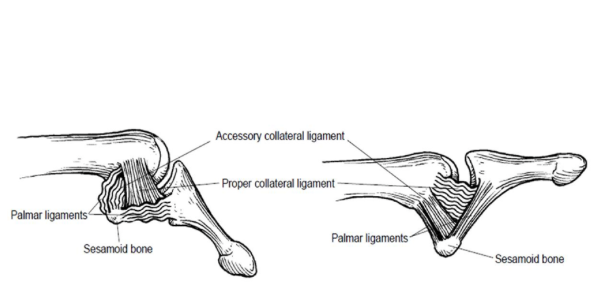

Describe the anatomy of the UCL?

- Proper collater ligament

- Runs MC head to volar aspect of prox phalanx

- resist valgus load w thumb in Flexion

- primary contraint in flexion

- Accessory collateral ligament & volar plate

- Runs palmar to proper ligament inserts into volar plate

- resist valgus load w thumb in EXTENSION

- Primary contrainst w volar plate in extension

- __Valgus laxity in both flexion and extension = complete UCL rupture